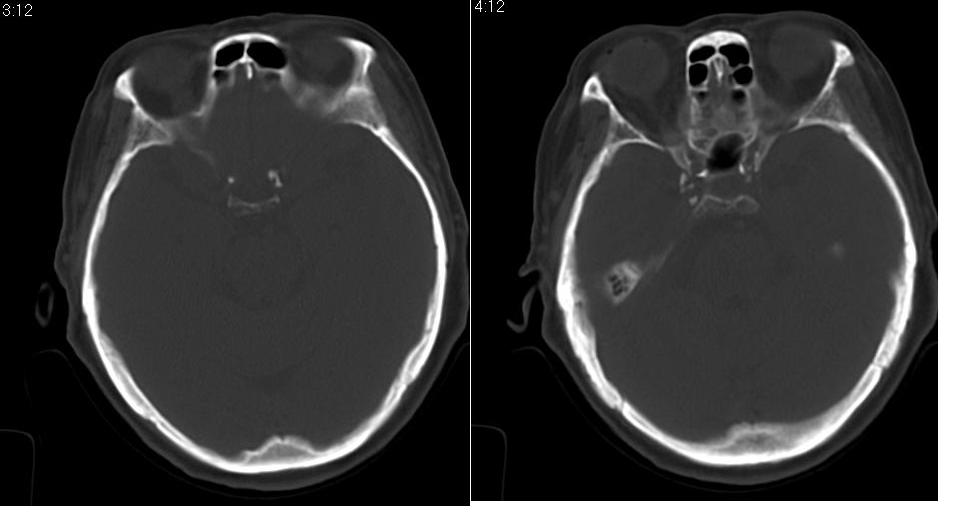

女 70岁,左侧上颌窦腔内肿物。

窦壁骨质增厚,密度增高,考虑慢性炎症,息肉样变。

左侧颌窦内可见高密度影充填,窦壁增厚 考虑 左颌窦囊肿 慢性炎症

左侧上颌窦内软组织影,略呈膨胀性,窦壁骨质增生硬化,考虑为黏膜下囊肿.左侧筛窦炎

左侧上颌窦内软组织密度影,窦壁骨质增厚,密度增高,窦口扩大,考虑左侧上颌窦慢性炎症,息肉样变。